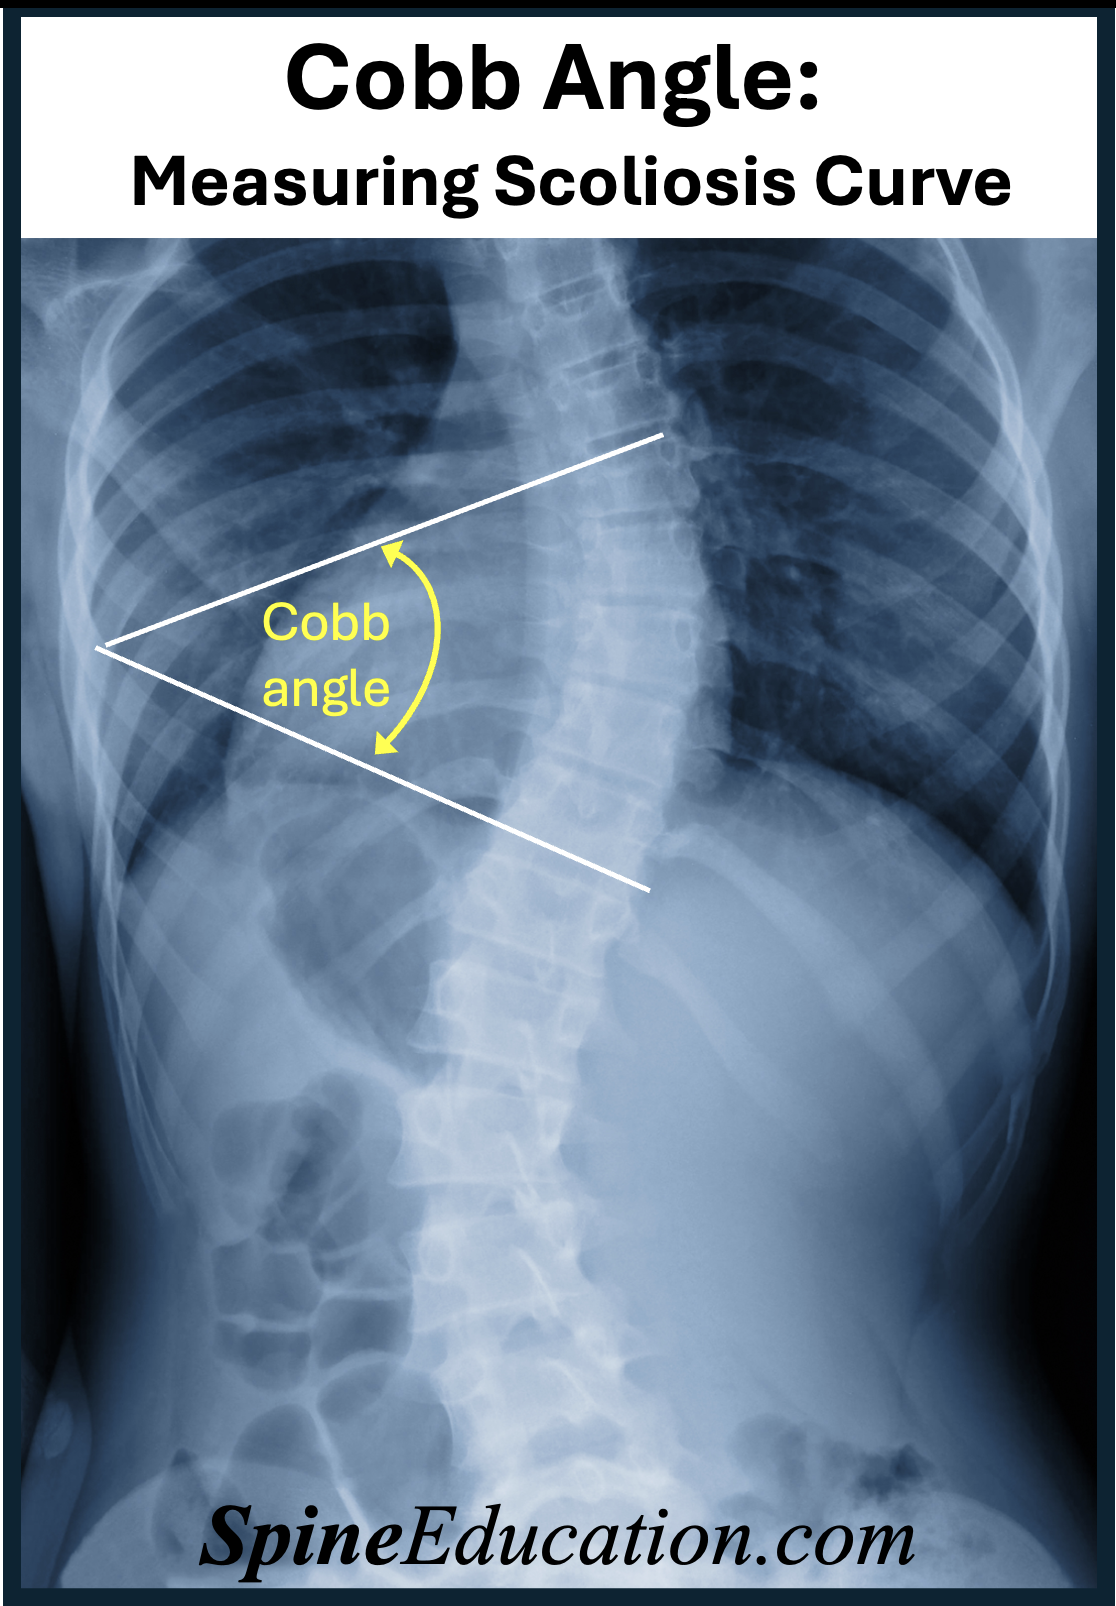

Understand how MRI and contrast dye work together to enhance diagnostic imaging. This guide explains why contrast agents are used during magnetic resonance imaging, the safety profiles of gadolinium-based contrast media, potential side effects, and what patients should expect during the procedure to ensure clear, accurate results for doctors.